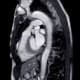

Ascending thoracic aortic disease is an important cause of sudden death in the U.S., yet most aortic aneurysms are identified incidentally. To improve assessment of patients who may be at risk for aortic dissection and rupture, researchers from UC San Francisco have developed a prediction model of aortic diameter to identify asymptomatic individuals with enlarged ascending aortic diameter.

In their study, which was published November 15 in the Journal of the American Medical Association (JAMA), the investigators developed and validated a clinical score to estimate ascending aortic diameter. Their prediction model was based on commonly available clinical covariates to identify symptomatic individuals with enlarged ascending aortic diameter, a risk factor for ascending aortic dissection.